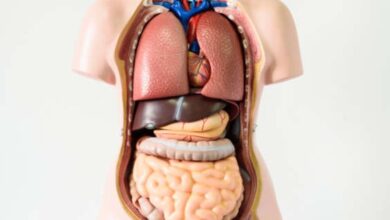

سلامت خانواده

نادرترین بیماری هایی که باعث مرگ می شوند

ریفلاکس معده ؛ یک عامل کمتر شناخته شده از پوسیدگی دندان

روش تشخیص کم خونی از پوست دست

خواص شگفت انگیز Jujube برای سلامت بدن

سردرگمی بیماران با “myasthenia gravis” ؛ هیچ کس پاسخ ما نیست/ “دارو برای رسیدن به آن طرف شهر کم است” “